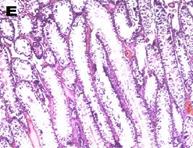

Histoarchitecture of the testes of treated animals showed mild to moderate atrophy and altered spermatogenesis (fig. 5). These were characterized by a reduction in the size of the seminiferous tubules and a decreased number of interstitial cells accompanied by spermatogenic arrest at high doses of the extract (fig. 5). The observations were in agreement with the reduced sperm numbers recorded.

Fig. 5: Photomicrograph (x40) showing histopathological profile of the testes of rat after 14 d treatment with varying doses of Carica papaya. A, B, C, D, E are control 10, 100, 300, 500 mg/kg of aqueous leaf extract of C. papaya respectively